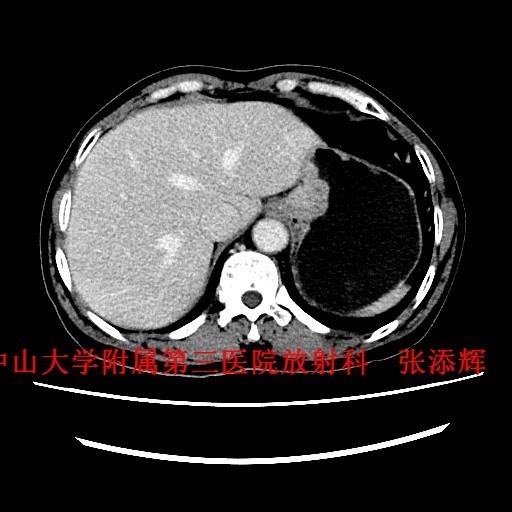

查体:全身浅表淋巴结未触及肿大。腹平软,无压痛、反跳痛。 辅查:1、胃镜:贲门Ca?;2、上腹部CT示:贲门胃底癌,浸润胃壁全层,小网膜囊多发稍大淋巴结。

诊断:贲门癌 治疗:排除手术禁忌征后,全麻下行“腹腔镜下根治性全胃切除术”。术中及术后病理诊断为“中-低分化腺癌,浸润胃壁全层,1/61枚淋巴结转移,分期T3NIM0,ⅡB期”。

讨论:贲门癌发病率和病死率均较高,临床上其诊断主要依靠胃镜检查+病理活检,然而CT检查也是贲门癌必不可少的术前检查,术前CT不仅能了解贲门癌病变局部情况,还可以观察周围结构及远处转移的情况,特别是对于淋巴结的转移,贲门癌淋巴结转移多位于贲门旁、胃小弯、胃左动脉及腹腔动脉周围淋巴结,平时读片是应该多注意这些部位的淋巴结是否肿大。 参考文献:Stein HJ,Feith M,Siewert JR. Cancer of the esophagogastric junction [J].Surgical Oncology,2000,9(01):35-41 .doi:10.1016/S0960-7404(00)00021-9 .